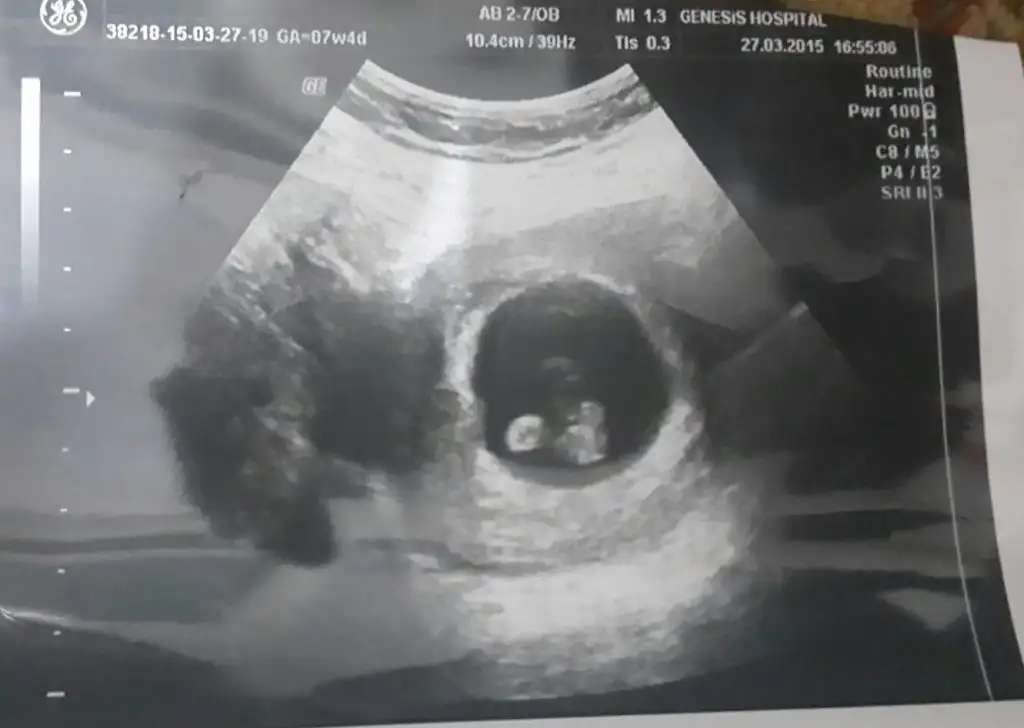

'Arkadaşlar bugün ultrasonda 6 bucuk haftalık oldugunu söyledi doktorum.Tahminde bulunabilirmisiniz..

Ikinci bebisim kısmet olursa, 5 yasinda bir cimcimem var saglikli olsunda gerisi önemli degil canım cin rus erkek gosteriyor bakalim hayirlisi artik